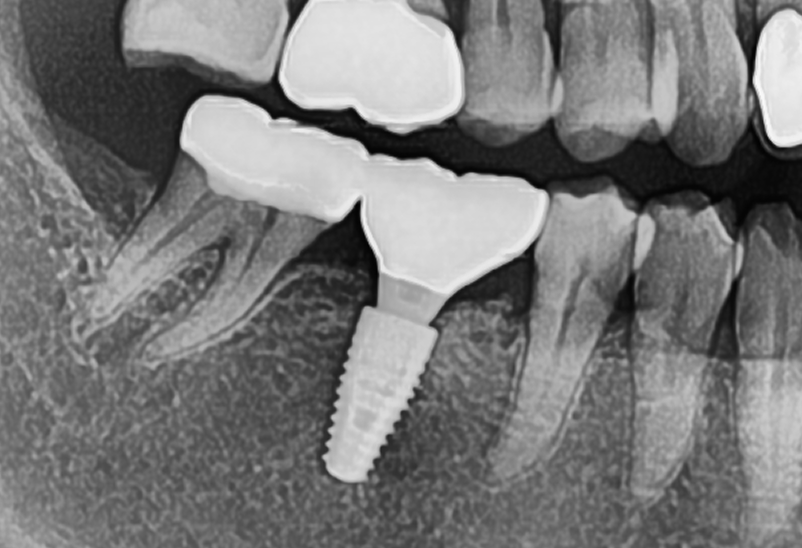

臼歯部(奥歯)の

インプラント治療

タップで写真の拡大ができます。

Before

After

主訴

奥歯で噛めない、歯茎が腫れてきた

治療内容

抜歯即時インプラント埋入1本、待時インプラント埋入2本、リッジプリザベーション(顎堤温存術)、GBR

治療期間

6〜8ヶ月

治療費用

1,947,000

治療の

リスク

オッセオインテグレーションが得られなかった場合、撤去、再度埋入の可能性